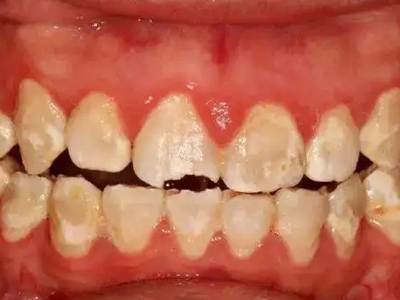

酸蚀症牙齿缺损不平整图

酸蚀症患者的牙齿会发生缺损,轻度时仅表现为牙齿尖端凹凸不平,有少量骨质缺失,缺损处有黄褐色至红褐色斑点,该病可能是长期接触外源性酸性物质而致病。